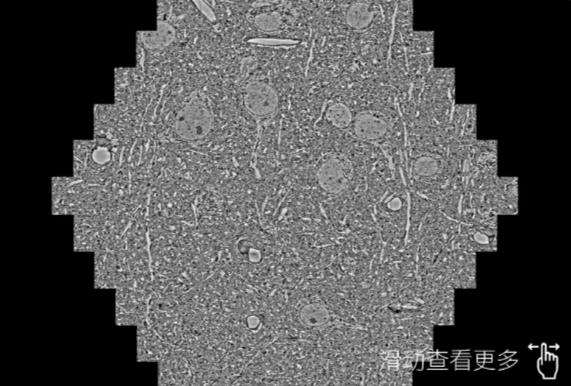

鼠脑切片。左图使用鄂尔多斯蔡司鄂尔多斯扫描电镜MultiSEM706对165μmx143pm面积区域成像,耗时仅需1.5秒。右图为鼠脑切片中30μm区域放大效果。样品由芝加哥大学B.Kasthuri提供。

使用蔡司高速鄂尔多斯扫描电镜MultiSEM对1mm²人脑皮层组织进行高分辨成像,并对其中的各种细胞结构进行三维重构分析。左图展示了2x3mm²组织平面中锥体神经元的三维重构效果。右图显示了局部体积神经元三维重构。图像由哈佛大学chtman实验室提供,渲染图由D. Berger 制作。